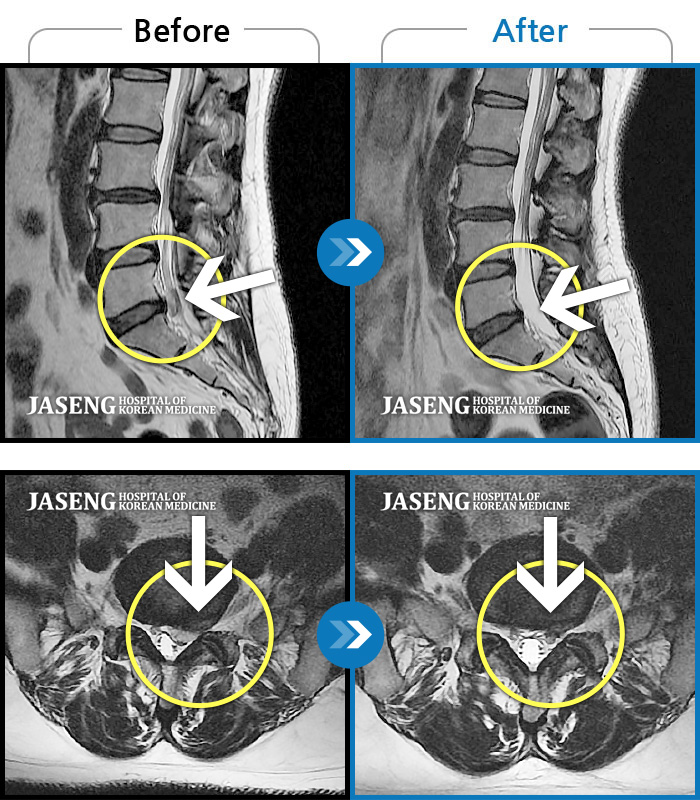

MRI 치료사례

왼쪽 종아리가 많이 당기고 걸을 때 절뚝거림이 심했습니다.